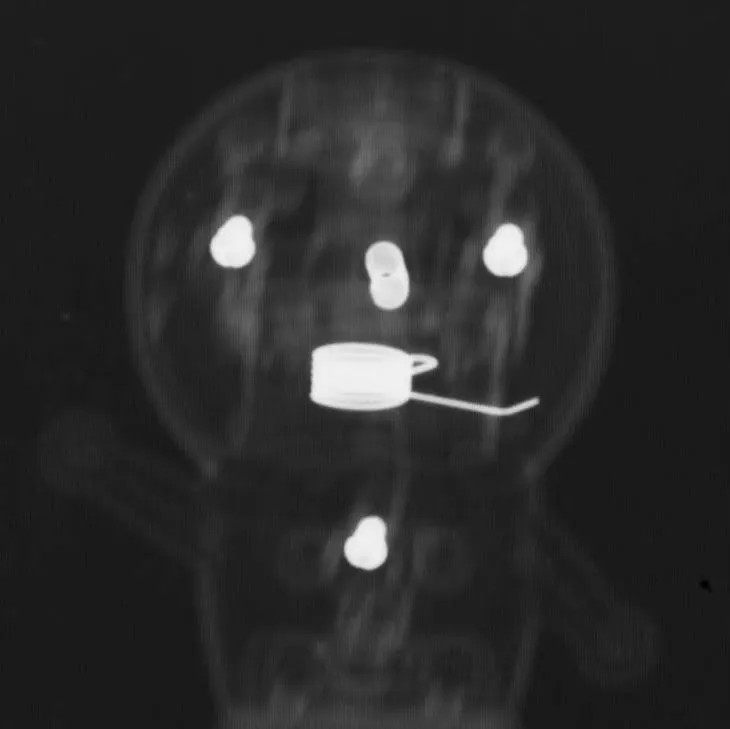

レントゲン撮影では骨、小石や金属はわかりやすいですが、ぬいぐるみやティッシュ、プラスチック等はかなり特殊な条件でないとわかりません。

写真は、ぬいぐるみとプラスチックのドラえもんのレントゲンです。金属ねじははっきりとわかりますが、ドラえもんの形など細部はぼんやりしており、写りにくいです。

【失敗】私の想定よりもぬいぐるみドラえもんが写ってしまいました。